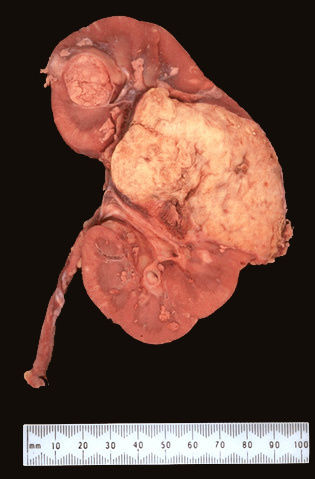

| Tumor de Wilms |

Image:

Renal058 (image/jpeg)